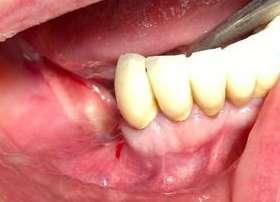

Le terapie riabilitative implantari per pazienti con edentulia parziale o totale, permettono di riportare sia la funzionalità che l’estetica, con una prevedibilità di successo che dipende, oltre che dall’efficace piano terapeutico chirurgico implantare del professionista chirurgo, anche dalla responsabilità attiva del paziente a seguire corretti stili di vita di igiene orale domiciliare e follow-up. Questi devono prevedere la visita diagnostica di controllo dell’implantologo e la visita di controllo dell’igienista dentale. Per sollecitare l’aderence ai follow-up, usare l'automazione workflow e moduli di anamnesi personalizzati (gestionale Alfa Docs) permette una migliore gestione e un monitoraggio efficace delle cure e dei richiami personalizzati in base ai bisogni extra clinici dei pazienti. La vera sfida è il management di igiene orale in pazienti presi in carico che sono stati sottoposti a terapie implantari in altri studi, e che mostrano clinicamente mucosite, con interessamento della mucosa perimplantare o con perimplantite che coinvolge l’osso di sostegno.

Spesso si evidenzia il collare implantare degli abutment, e prima che l’implantologo preveda intervento mucogengivale è fondamentale condividere con il paziente la necessità di eliminare l’infiammazione eseguendo un'igiene orale domiciliare attenta ed efficace. L'igiene orale domiciliare deve essere considerata terapia.

Bisogna accertarsi che non sia presente pus, sintomo predittivo di perimplantite e probabile perdita ossea, che va valutata dall’implantologo radiograficamente, con particolare attenzione alla perdita ossea interprossimale. Se presente, è importante l’approccio motivazionale di concordance con la persona assistita per responsabilizzarlo al controllo del biofilm batterico degli spazi interprossimali

Successivamente alla diagnosi ricevuta dall’implantologo e le indicazioni sul piano terapeutico scelto, capita spesso di intervenire con una terapia di supporto palliativa, che ha l’obbiettivo di mantenere le condizioni della riabilitazione in buon stato clinico. L’ascolto del paziente è fondamentale per accogliere i disturbi percepiti dal paziente quali disestesia, sensazione di corpo estraneo o dolore.

L’uso di ablatori che permettano in maniera ergonomica di erogare deplaquing e debridment con la possibilità di scelta di differenti punte per un migliore adattamento alla superficie sono ideali per una terapia parodontale non chirurgica efficiente, ed un timing operativo agevole per l’ope-

ratore e per il paziente (Combi Touch Mectron). Il sondaggio parodontale permette la diagnosi della malattia perimplantare e va eseguito con una sonda in materiale plastico con delicatezza ed una forza controllata di 0.25 N, per evitare danni alla mucosa perimplantare. In caso la sonda evidenzi una tasca perimplantare, può essere usato il gel Perioral 3 (GEMAVIP) all’olio di oliva ozonizzato.